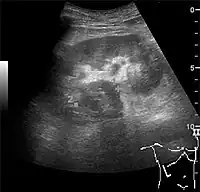

Complex cysts can have membranes dividing the fluid-filled center with internal echoes, calcifications or irregular thickened walls. The complex cyst can be further evaluated with Doppler US, and for Bosniak classification and follow-up of complex cysts, either contrast-enhanced ultrasound (CEUS) or contrast CT is used (Figure 6). The Bosniak classification is divided into four groups going from I, corresponding to a simple cyst, to IV, corresponding to a cyst with solid parts and an 85–100% risk of malignancy.[1] In polycystic kidney disease, multiple cysts of varying size in close contact with each other are seen filling virtually the entire renal region. In advanced stages of this disease, the kidneys are enlarged with a lack of corticomedullary differentiation (Figure 7).[1]